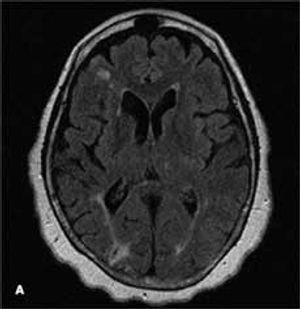

A 68-year-old woman with a history of hypertension, hyperlipidemia, and tobacco use presented with her third stroke in the past 7 years. Neurological deficits included dysarthria and left-sided motor and sensory loss. A previous transthoracic echocardiogram with a bubble study did not reveal any cardiac source of embolism. Axial MRI of the brain on admission showed an abnormal signal in the bilateral hemispheres representative of multiple subacute infarcts